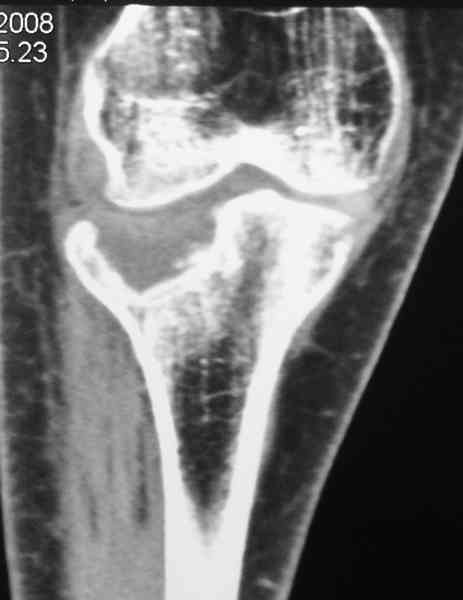

По тактике лечения, более импонирует второй вариант, но наружная плато расколота и туда при нагрузке внедряется н/мышелка бедра, поэтому после дистракции как репонирвать: или стяжными винтами, или изогнутами спицами или субхондральная костная пластика?

Уважаемый Абдурашид. Если нет противопоказаний , то из оперативных способов, я бы рекомендовал следующие: Полное замещение наружного мыщелка аллотрансплантатом либо открытая репозиция с элевацией и замещение дефекта ауто или аллокостью. В Ваших условиях , я бы рекомендовал второй способ. Во-время элевации необходимо разъединить фрагменты со стороны сустава ( надсечь скальпелем по линиям перелома, а затем тонким остеотомом их разъединить. При помощи долота произвести неполную остеотомию ( захватите не менее 1,5 - 2 см губчатой кости и поднять фрагменты, визуально отрепонировать и фиксировать 2-3 спицами. Дефект заместить костным ауто или аллатрансплантатом. Окончательная стабилизация пластиной ( лучше с угловой стабильностью, либо АВФ - позволит спокойно устранить угловую деформацию.

Недавно поступила больная через 1,5- 2 месяца.